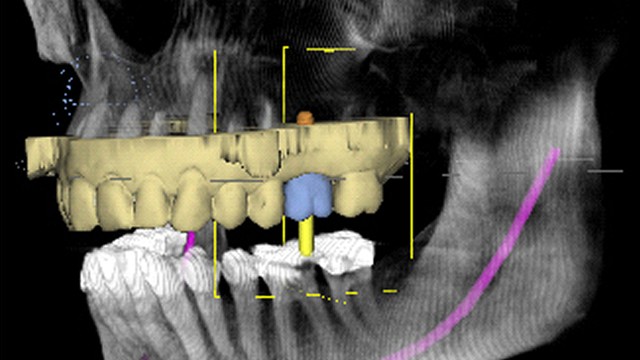

The digital implant is checked in three dimensions to determine proper functionality with the crown and avoidance of the patient’s maxillary sinus.

Once the implant is placed digitally in the proper position the data is sent to our CAD CAM machine to design and mill a surgical guide for placement of the implant for the upper left.